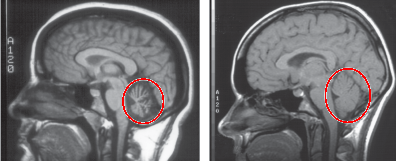

진단명: 알코올성 소뇌위축증

-소뇌는 몸의 균형과 움직임을 조절하는 뇌 부위

-만성 음주는 소뇌를 서서히 파괴하고

결국 걷기 장애, 손떨림, 어지럼증으로 이어집니다.